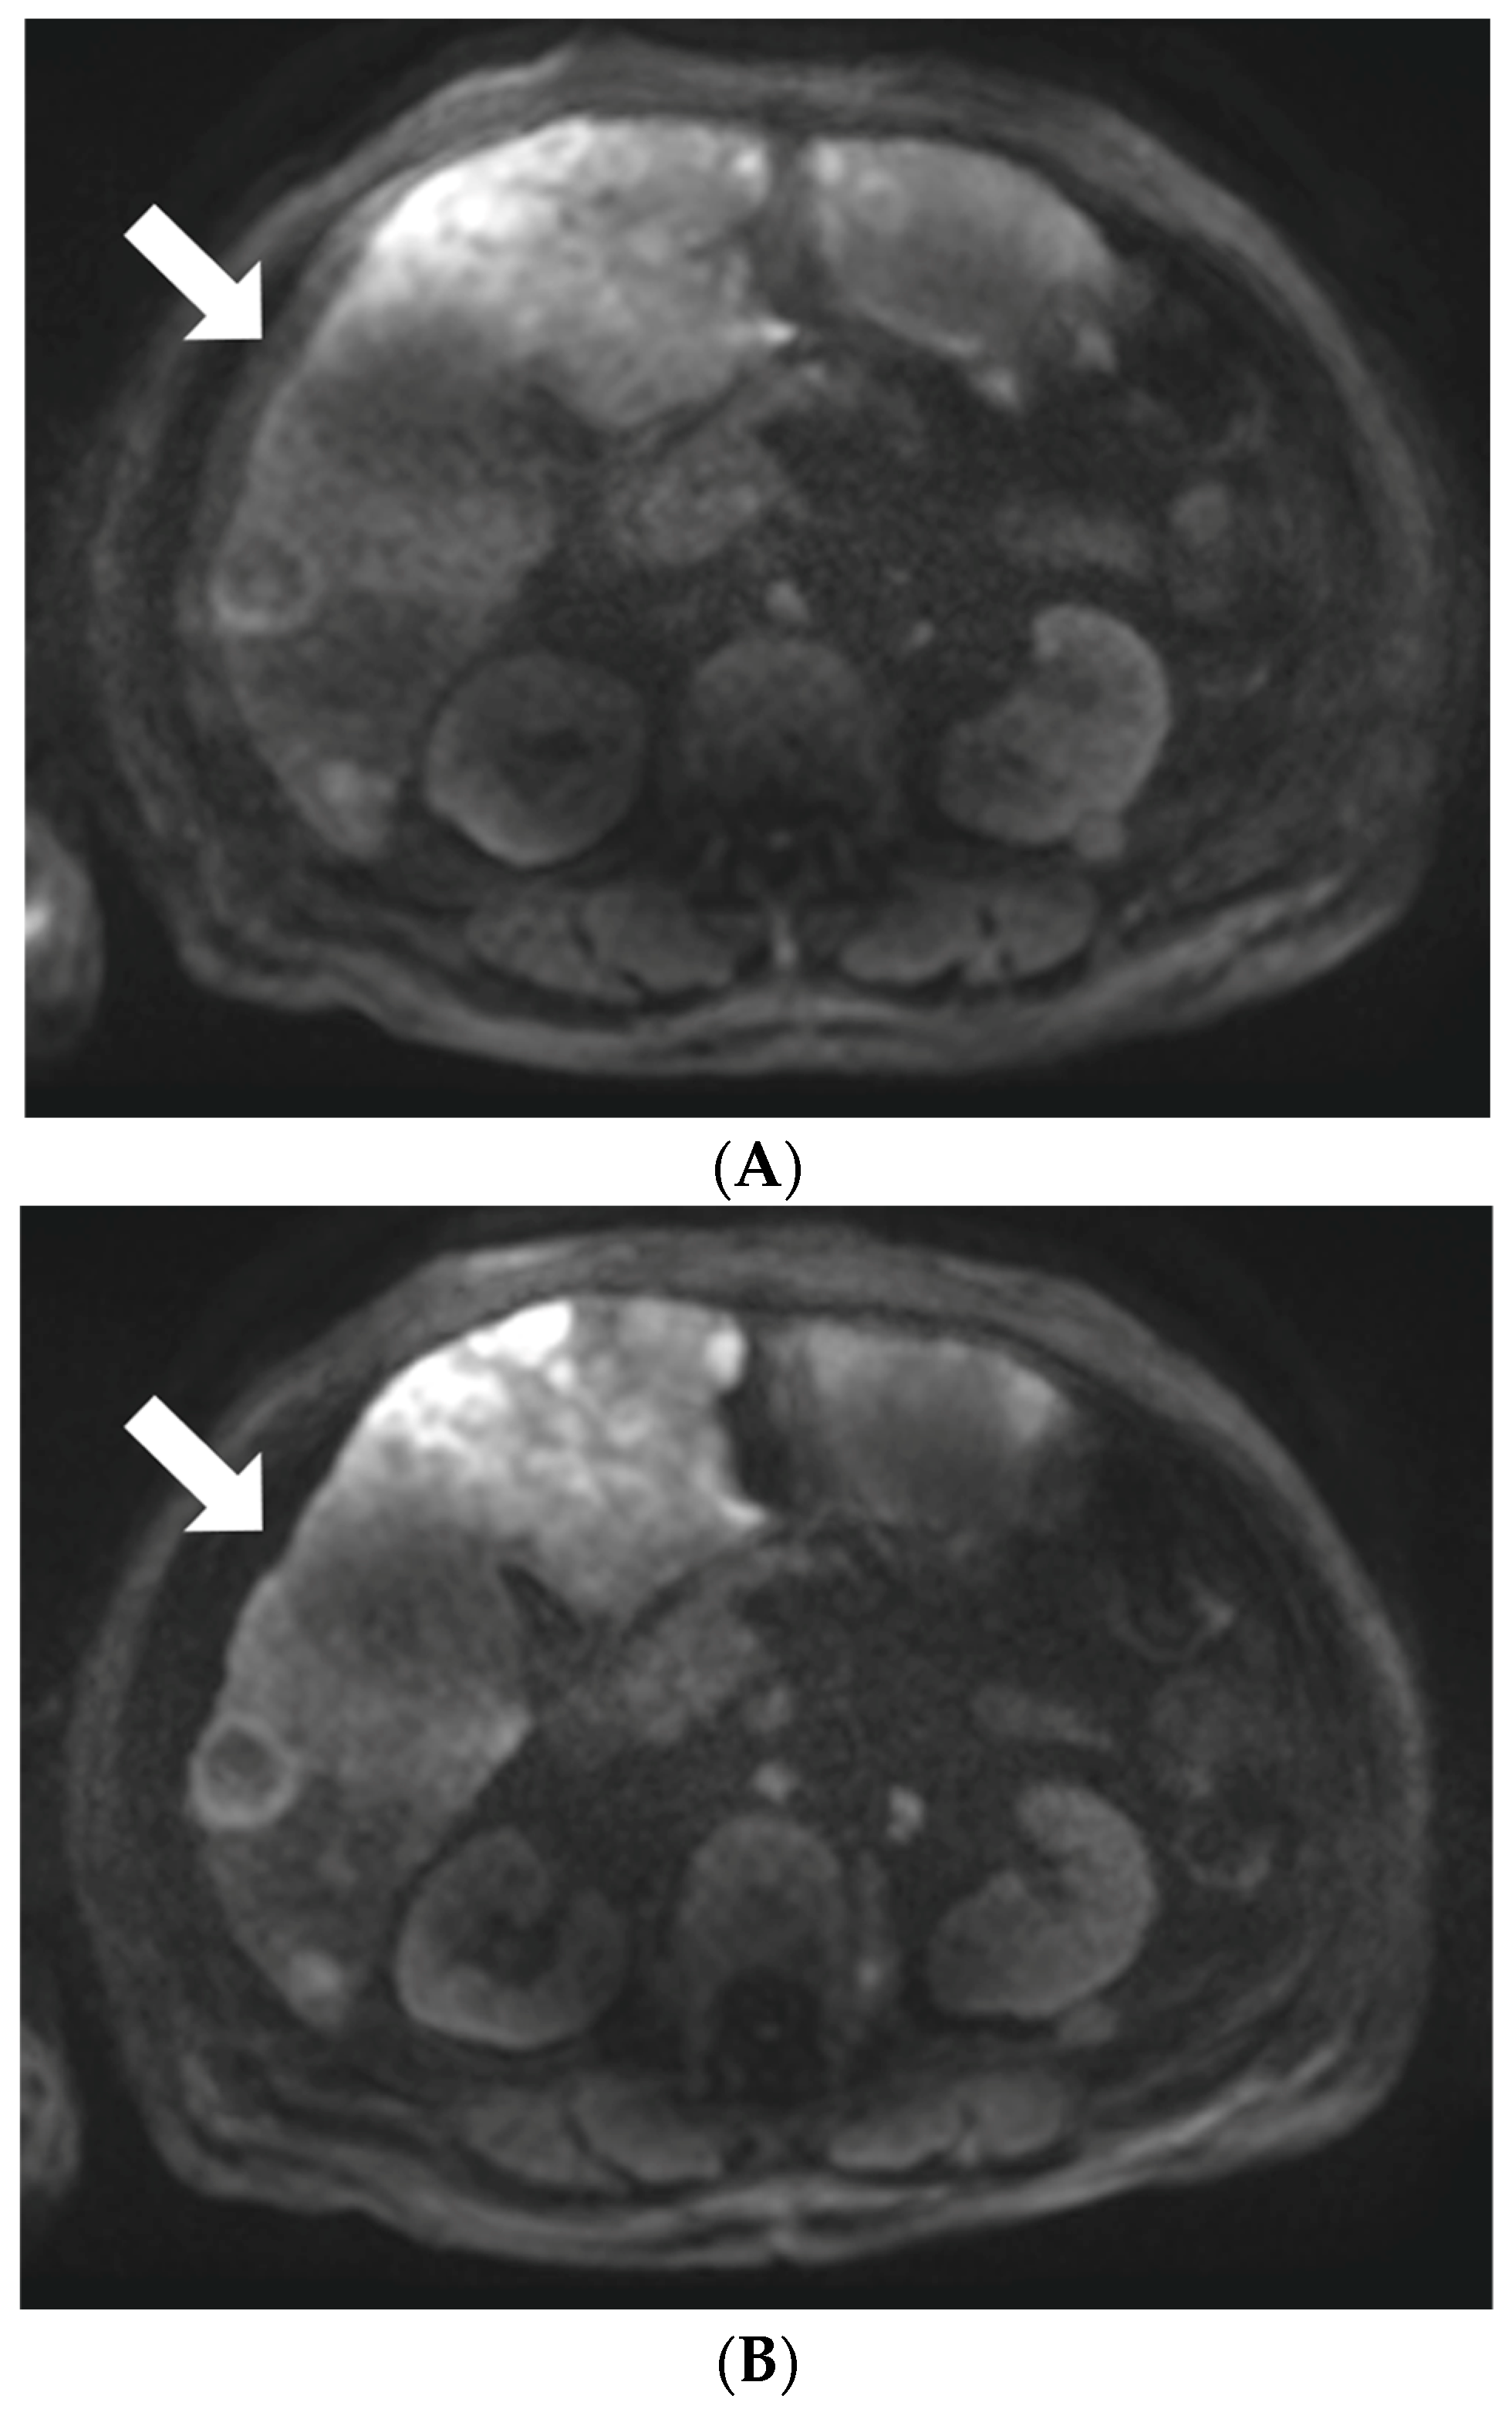

3.2. Lesion Visibility and Conspicuity